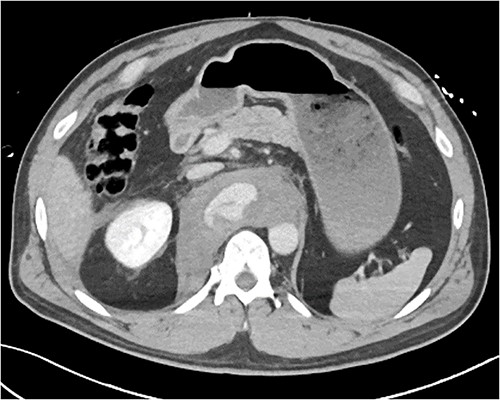

A 54-year-old male presented to our Level 1 Trauma Centre following a high-speed motor vehicle accident with rollover. Although initially haemodynamically stable, significant hypoxia prompted a trauma call activation. On arrival to the Trauma Centre, he had a Glasgow Coma Scale of 8 with an initial heart rate of 70 bpm and systolic blood pressure of 101 mmHg. A brief loss of cardiac output resulted in intubation, bilateral finger thoracostomies and the commencement of massive transfusion. Although his abdominal eFAST was positive, he was fluid responsive and proceeded to imaging. A full computed tomography (CT) trauma series demonstrated CA avulsion (Fig. 1) with contrast extravasation into the retroperitoneum and a large retroperitoneal haematoma measuring 18 cm by 9 cm (Figs 2 and 3). Nil visceral injury was identified and imaging otherwise revealed fractures of the left scapula, right 12th rib and bilateral acetabula and pubic rami.

Axial CT slice demonstrating coeliac trunk avulsion with active bleeding into a large retroperitoneal haematoma.

Coronal CT slice demonstrating coeliac trunk avulsion with active bleeding into a large retroperitoneal haematoma.